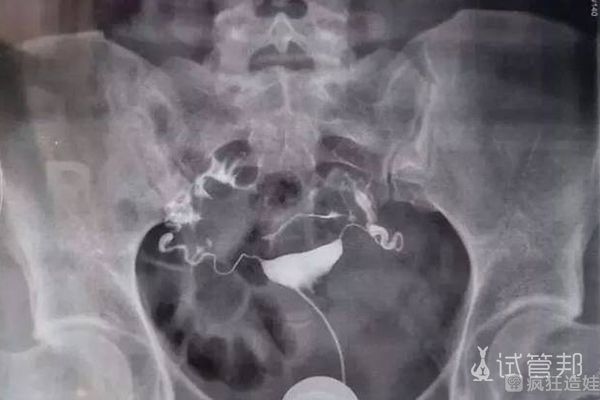

这次打了降调,顺利启动促排,由于卵巢功能差,也不咋吸收,期间换了2种药促排,还加大了剂量,光是促排打了13天,第15天安排取卵。取卵当天人不多,我是第一个取的,之前取过知道流程,相对来说没那么紧张。一共取了8个卵子,比第一次多了近一半,手术时候也顺便把囊肿给穿刺了。

成功受精了5个胚胎,有2次胚胎移植机会。因为我想先好好调理下身体,所以过了3个月才进入周期等待胚胎移植。走的是自然周期,非常顺利胚胎移植了2个A级解冻后的胚胎。结束后躺了有近半个小时才回去,老公特地每天早点下班回来陪我,担心我一个人在家胡思乱想。